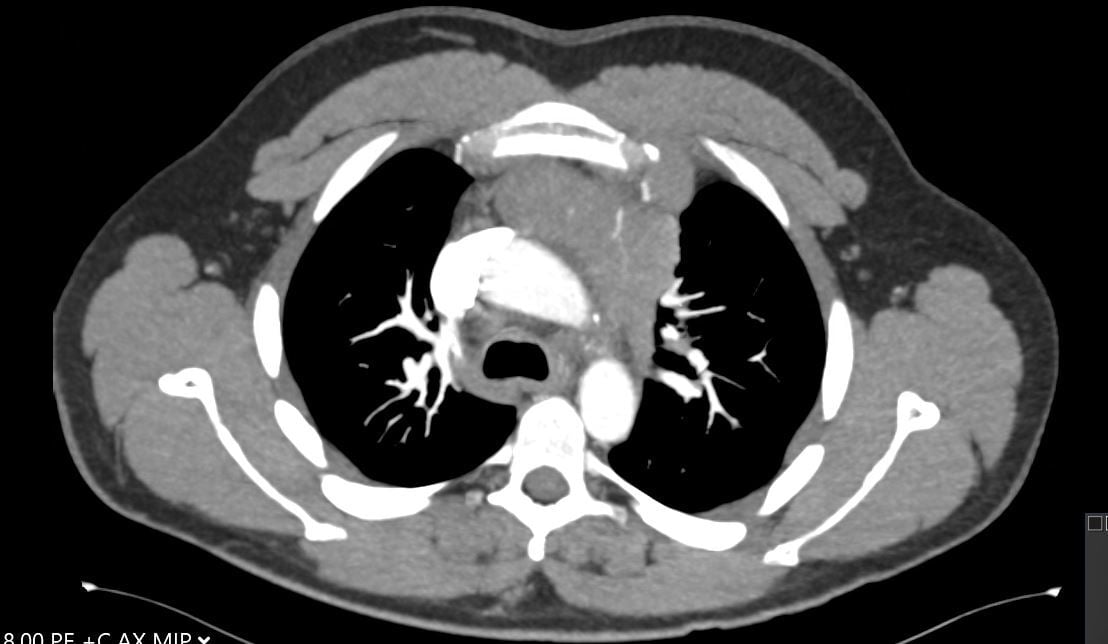

A 30-year-old man presents with dyspnea and is found to have an anterior mediastinal mass, as well as supraclavicular lymphadenopathy; biopsy of the mass is consistent with thymic carcinoma. Imaging shows his anterior mediastinal mass, lung and diaphragmatic lesions consistent with metastatic malignancy, and probable pericardial involvement with small pericardial effusion (Figures 1, 2, 3, and 4).

Fig. 3: CT image showing large mediastinal mass found to be thymic carcinoma. -

Fig. 4: CT image showing small pericardial effusion. -